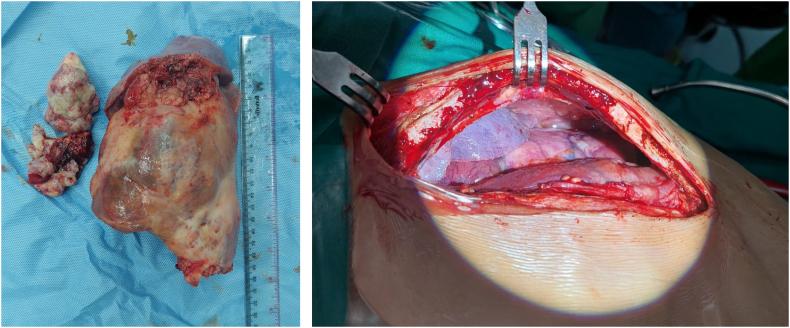

Total removal of the tumor was performed, aided by cardiopulmonary bypass. Type III PPB was confirmed histopathologically.

在体外循环辅助下进行了肿瘤全切术。组织病理学确诊为III型PPB。